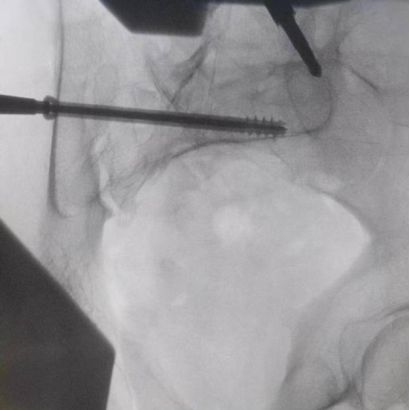

據(jù)了解,患者37歲,為高墜傷患者,入院合并顱腦挫傷、盆腔臟器出血、骨盆骨折多發(fā)傷患者。為最大限度降低手術風險,同時給予患者滿意的手術療效,術前綜合評估患者病情,擬定行“天璣機器人”輔助定位下骨盆骨折微創(chuàng)手術。2月13日10時,手術正式開始。拉薩市人民醫(yī)院采集患者術中二維影像,通過骨科手術機器人擬定螺釘打入位置方向后,吳宏華主任完成手術設計,成功為該患者置入了一顆高難度骶髂螺釘,出血5ml,切口1cm。術后圖像顯示,螺釘位置及方向完全符合手術規(guī)劃,沒有一絲偏差,手術最終獲得圓滿成功。

圖為透視下見置入的骶髂螺釘,位置、長度精準,無絲毫偏差